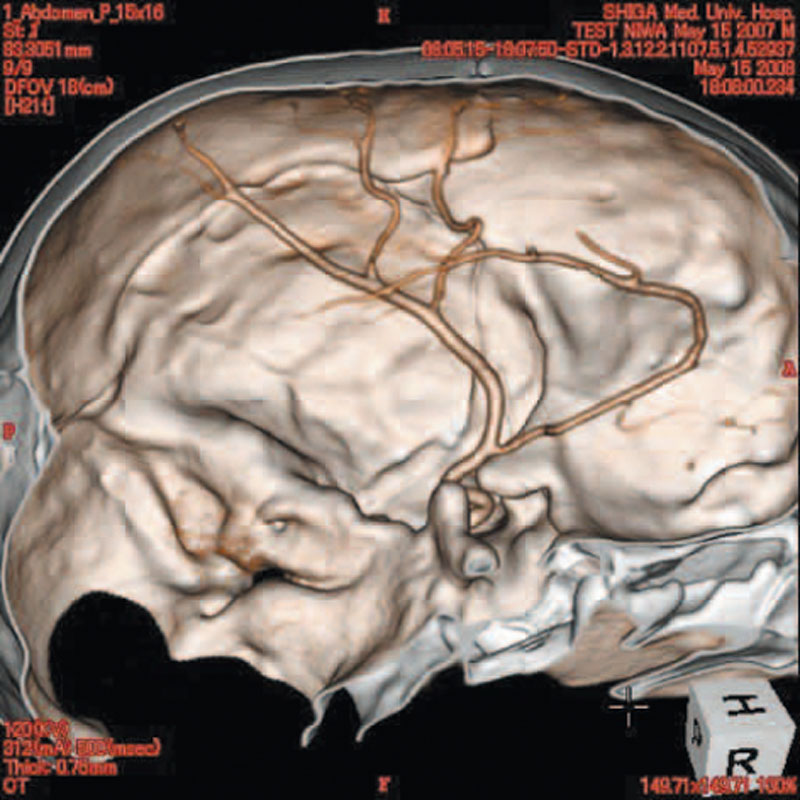

Ein einzigartiges Ganzkörperphantom für CT bietet eine Vielzahl von Ausbildungs- und Forschungsmöglichkeiten. Das Phantom kann auch für normales Röntgen benutzt werden und gibt lebensnahe Bilder. Es benden sich keine Metallteile oder Flüssigkeiten im Phantom. Die wichtigen Gelenke haben eine menschenähnliche Beweglichkeit und erlauben vielfältige Positionen für die Übung. Das Phantom kann in 10 Teile zerlegt werden. Die verbesserten Schultergelenke erlauben es, die Arme nach oben zu bewegen. Die künstlichen Organe sind anatomisch korrekt und haben entsprechende HU-Zahlen.

- Synthetischer Schädel

- Gehirn

Radiologische Absorption und Hounsfield-Nummer ähnlich dem menschlichen Körper.